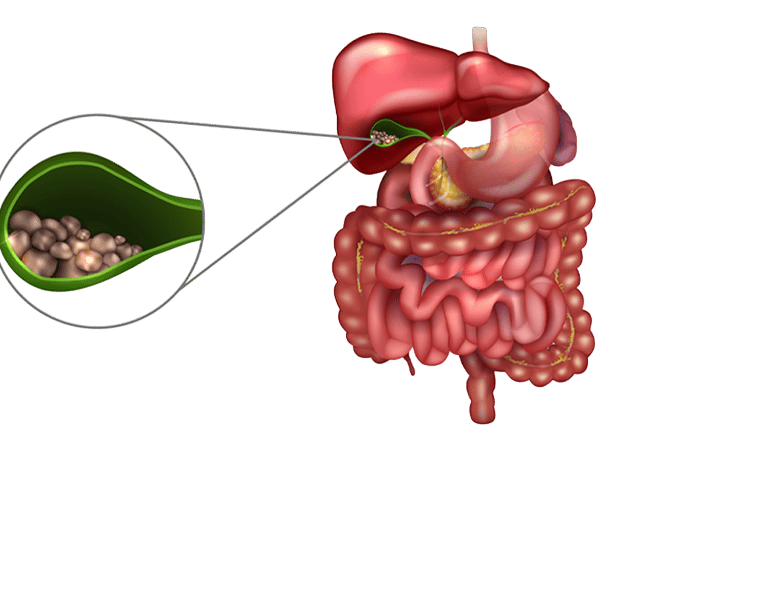

Cálculos biliares são pequenas “pedras” que se formam dentro da vesícula biliar — um órgão localizado abaixo do fígado e responsável por armazenar a bile, um líquido que ajuda na digestão das gorduras. Essas pedras podem ter composição variada, sendo a maioria formada por colesterol. Em alguns casos, estão associadas a infecções ou alterações metabólicas.

A relação anatômica entre vesícula, via biliar e pâncreas. Um cálculo de vesícula pode migrar por entre essas estruturas, provocando as complicações da doença

A vesícula biliar pode acumular cálculos, na sua maioria formados por colesterol